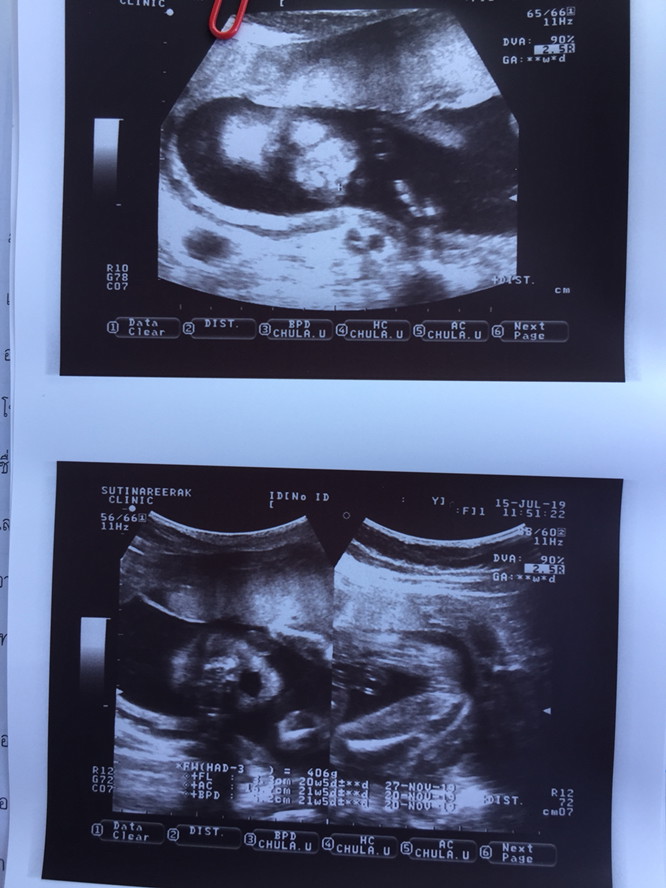

ขอดูภาพอัลตร้าซาวที่ระบุว่าเพศหญิงของแม่ๆหน่อยค่ะ พอดีเราพึ่งไปซาวด์มาหมอบอกว่า ญ เราอยากแน่ใจว่าทรงเดียวกันมั้ยค่ะ ?

รูปล่างขวามือค่ะแม่ เป็นกลีบเลย🤣🤣